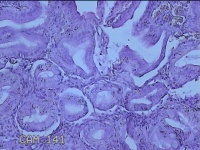

胃窦粘膜

性别

女

年龄

30岁

临床诊断

慢性胃炎;胃食管反流

一般病史

上腹部疼痛1周余。

标本名称

大体所见

灰白粉红色组织小米大一团。

片子这个效果,诊断起来比较困难。